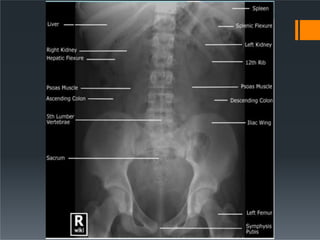

Abdominal Organs

ď‚§ Liver

ď‚§ right upper quadrant

ď‚§ extends to the hemidiaphragm and past the midline

 Chilaiditi’s syndrome

ď‚§ Spleen

ď‚§ left upper quadrant

ď‚§ extends to the hemidiaphragm

ď‚§ Its lower pole may be outlined by fat

ď‚§ Measurement of its length from the dome of the diaphragm

to the tip. This is usually less than 14 cm

ď‚§ Relationship of the spleen to the ninth, tenth and eleventh

ribs

ď‚§ Normal gallbladder or biliary system are not visible. Gas

ď‚§ Psoas muscle

ď‚§ symmetrical triangles either side of the lumbar spine

ď‚§ Stomach

ď‚§ left of midline, beneath hemidiaphragm

ď‚§ Kidneys

ď‚§ sit on the psoas muscles at level of T12 to L3

Bones and Joints

ď‚§ Spine

ď‚§ lower thoracic and lumbar spine should be of similar height

ď‚§ intervertebral disc spaces should be similar

ď‚§ spinous processes should be visible

ď‚§ Lower ribs

ď‚§ Sacrum and pelvis